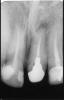

Hercule Опубликовано 25 ноября, 2012 Автор Поделиться Опубликовано 25 ноября, 2012 28 ноября :Апрель перед резекцией:Май после резекции:Июль после резекции: Скриншоты от 3Д Ссылка на комментарий